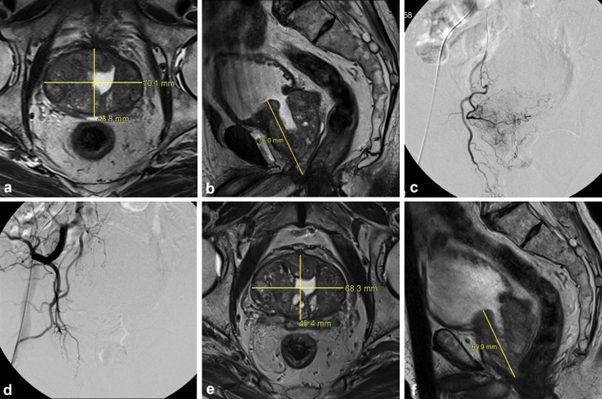

The procedure consisted of digital subtraction angiography of the prostatic arteries (PA) and its pelvic anastomoses followed by Polyvinyl alcohol (PVA) particle complete embolization of both prostate arteries (90–180 μm (n=9) or 180–300 μm (n=6)). A foley balloon was placed in the bladder to obtain optimal visualization.

The intervals from TURP to recurrent symptoms and from TURP to PAE were 4.3 y ± 3.2 and 5.6 y ± 3.8, respectively. Technical success was achieved in all patients. The clinical success rate for LUTS relief at 12 mo was 93.3% (14 of 15). IPSS significantly reduced from 22.5 ± 4.1 at baseline to 9.9 ± 4.9 at 12-mo follow-up, and QoL score improved from 4.7 ± 1.0 to 2.1 ± 1.1 (P < .05 for both). There was a significant mean reduction of 26.6% in PV at 12 mo, improving from 100.7 cm3 ± 38.5 to 73.9 cm3 ± 29.4 (P < .05).

Fig. 2. MR imaging and DSA in an 83-year-old man. (a) Axial imaging revealed an enlarged prostate gland with a prostatic resection cavity before PAE. (b) Sagittal imaging revealed a vertical diameter of the prostate (PV, 135.2 cm3). (c) Right iliac artery angiography showed the PA arising from the internal pudendal artery. (d) Postembolization angiography showed occlusion of the right PA. (e) Axial MR image at 3 months after PAE revealed a reduction of PV. (f) Sagittal MR image at 3 months after PAE revealed a vertical diameter (PV, 112.7 cm3; change from baseline, 16.6%).